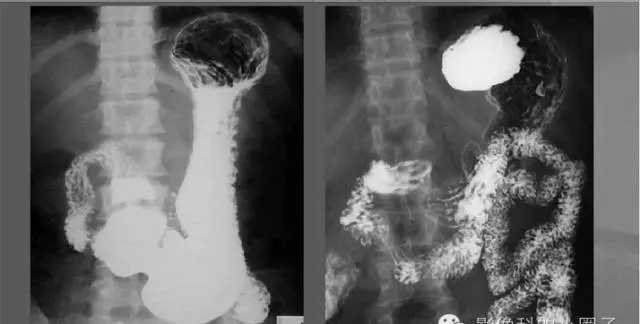

小肠造影

连续性排列;均匀、整齐;推进性蠕动;肠壁柔软、活动度好;7—9小时排空。

球部:三角形,穹窿对称、光滑、整齐、粘膜皱襞纵行、平行。

降部、水平部、升部:粘膜皱襞呈羽毛状,与空肠相似。